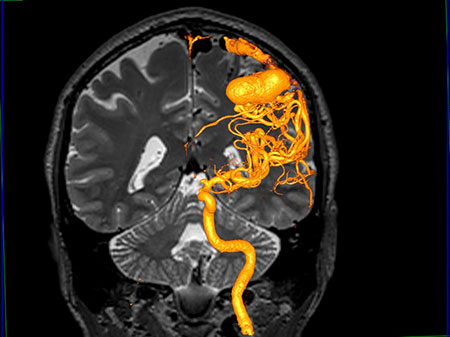

We use the latest diagnostic imaging, such as CT angiogram and catheter-based conventional angiography as well as CT angiography which avoids the risks of catheter techniques, to quickly and accurately diagnose your condition. Our treatments for aneurysms can include open operation (clipping), which involves placing a clamp on the neck of the aneurysm. In addition, we offer non-surgical endovascular treatments

Endovascular Neurosurgery

This is a radiology procedure that looks at how blood is flowing in the brain.

Conditions such as cerebral aneurysms, vascular malformations, vascular tumours, strokes and stroke related symptoms can be diagnosed with a cerebral angiogram

Arteriovenous malformations (AVM)

Arteriovenous malformations are abnormal collections of blood vessels, where arteries are directly connected to veins. Normally blood flows through arteries under high pressure to supply all of the organs of the body including the brain. From the arteries, blood passes through thin-walled capillaries to supply oxygen and nutrients to the tissue of the brain and then enters the veins under low pressure to be carried back to the heart and lungs.

In an AVM, the blood flows from the arteries directly to the veins. There is no capillary bed. Without a capillary bed, the AVM blood vessels have an increase in flow and blood pressure. Over the years this causes them to dilate and become thin-walled, and more likely to break and bleed.

An AVM can cause headache, weakness, numbness, visual problems, or seizures. Patients often first show symptoms when there is a bleed or rupture from one of the blood vessels making up the AVM.

An AVM is often diagnosed with a CT scan or MRI. A patient usually requires an angiography to then fully identify the anatomy of the AVM and make decisions about treatment.

AVMs may be treated using three different treatment methods. These methods are embolization, surgery and radiation therapy or radiosurgery.

Endovascular treatment of AVMsis available at FV Hospital. One innovative form of treatment involves use of a “super glue” substance introduced via a tiny catheter to reduce the size of the AVM and facilitate further microsurgical or radiation treatment. In some cases, it is possible to completely block off and cure the AVM with endovascular treatment alone.